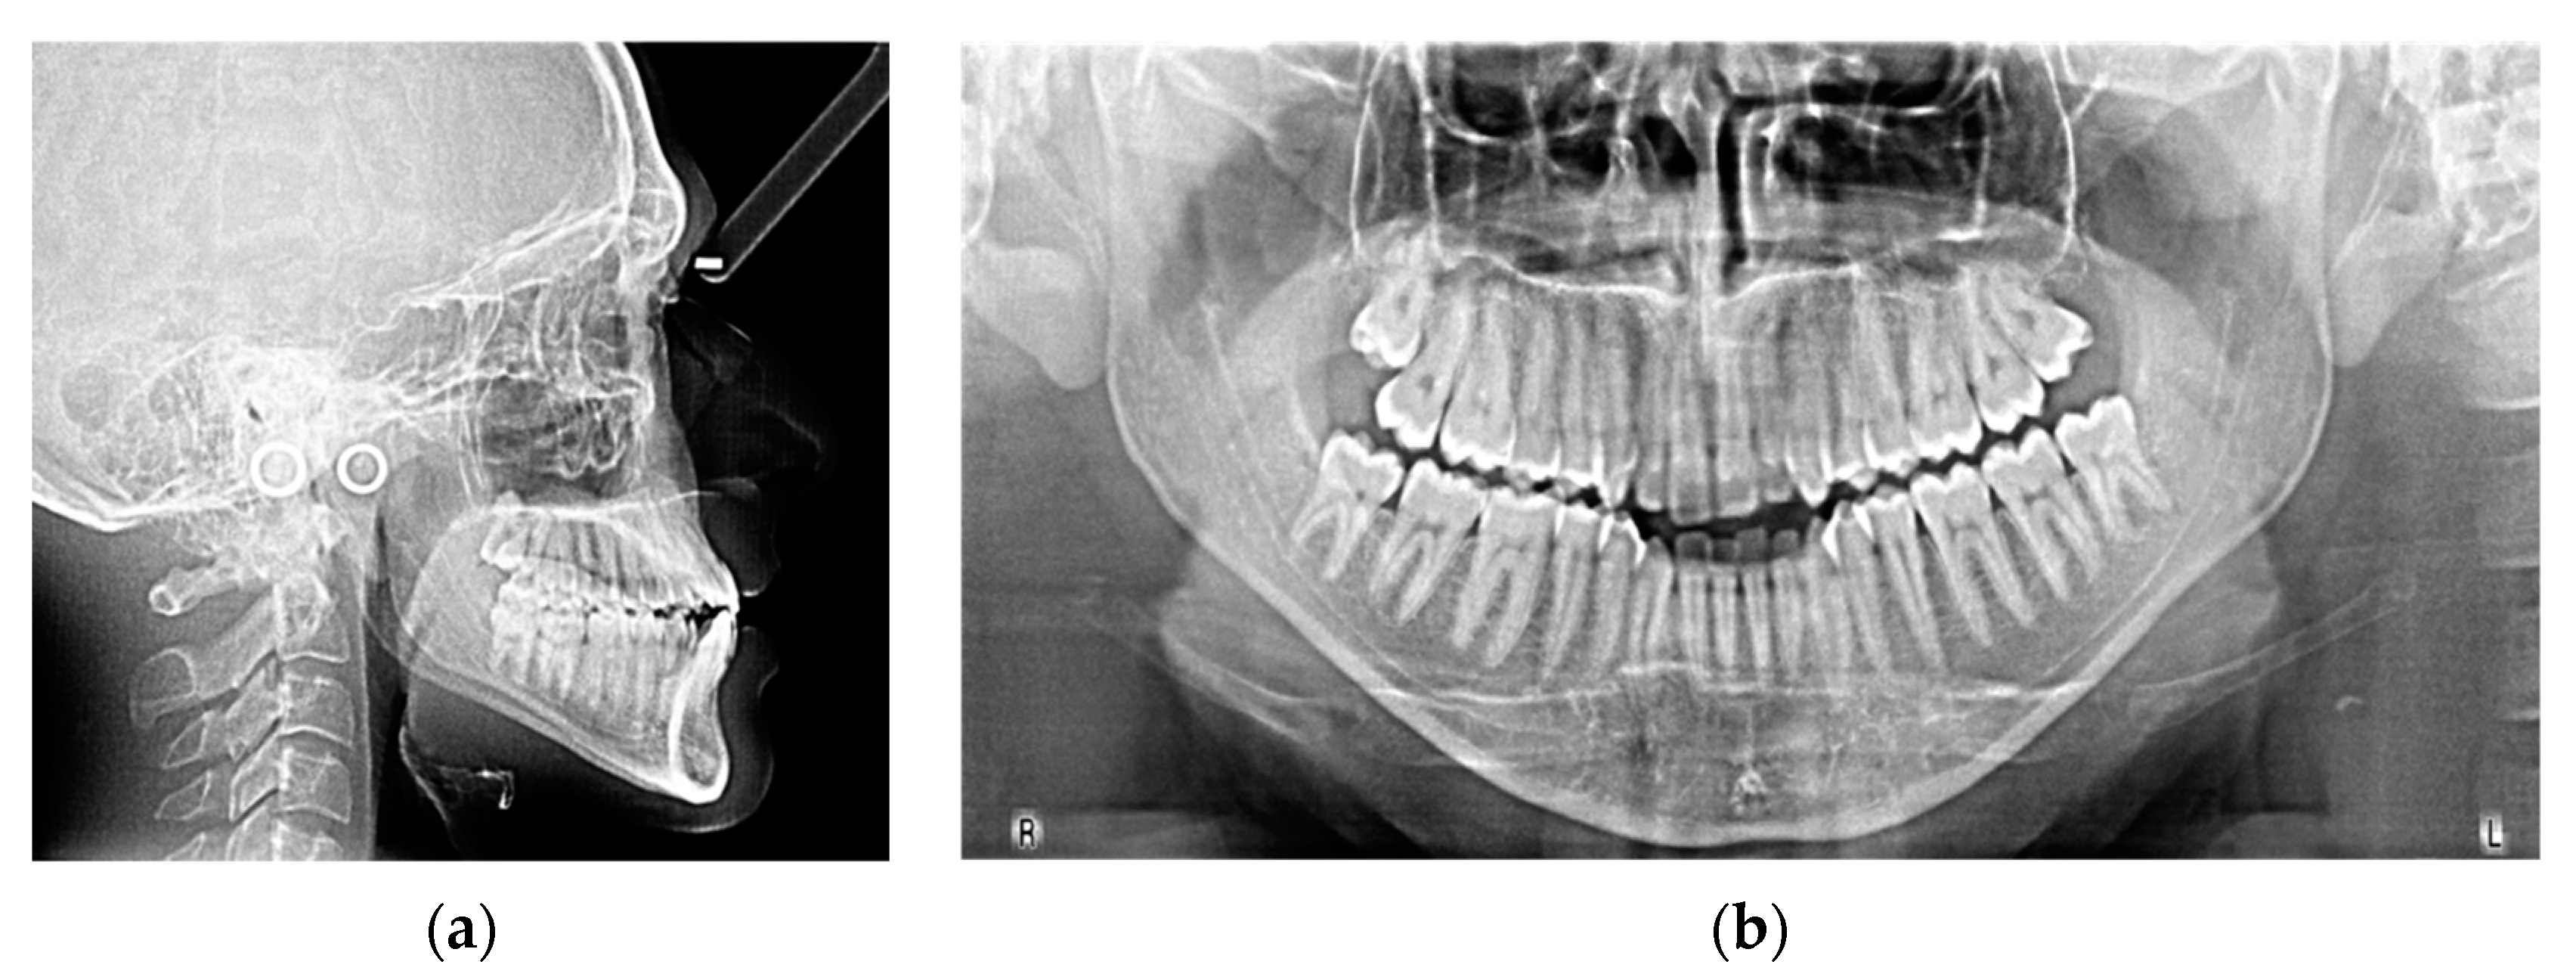

| Measurements | Initial | Final | Norm |

|---|---|---|---|

| SNA (°) | 86.7 | 87.5 | 82.0 ± 3.5 |

| SNB (°) | 84.1 | 84.9 | 80.0 ± 3.5 |

| ANB (°) | 2.6 | 2.6 | 2.0 ± 2.5 |

| SN^ANS-PNS (°) | 7.2 | 6.3 | 8.0 ± 3.0 |

| SN^GoGn (°) | 37.7 | 37.7 | 33.0 ± 2.5 |

| ANS/PNS^Go-Gn (°) | 33.3 | 33.3 | 25.0 ± 6.0 |

| U1^ANS-PNS (°) | 113.2 | 111.8 | 110.0 ± 6.0 |

| L1^GoGn (°) | 85.1 | 80.4 | 90.0 ± 6.0 |

| L1 Protrusion (L1-APo) (mm) | 1.6 | 1.3 | 1.0 ± 2.5 |

| Overjet (mm) | 2.6 | 2.4 | 2.5 ± 2.5 |

| Overbite (mm) | 0.6 | 1.5 | 3.0 ± 2.5 |

| U1^L1 (°) | 131.1 | 136.4 | 135.0 ± 6.0 |

| Co-Go-Me (°) | 123.9 | 124.8 | 125.0 |

| Lower lip to Ricketts E-line (mm) | −4.8 | −5.6 | 0.0 ± 2.0 |